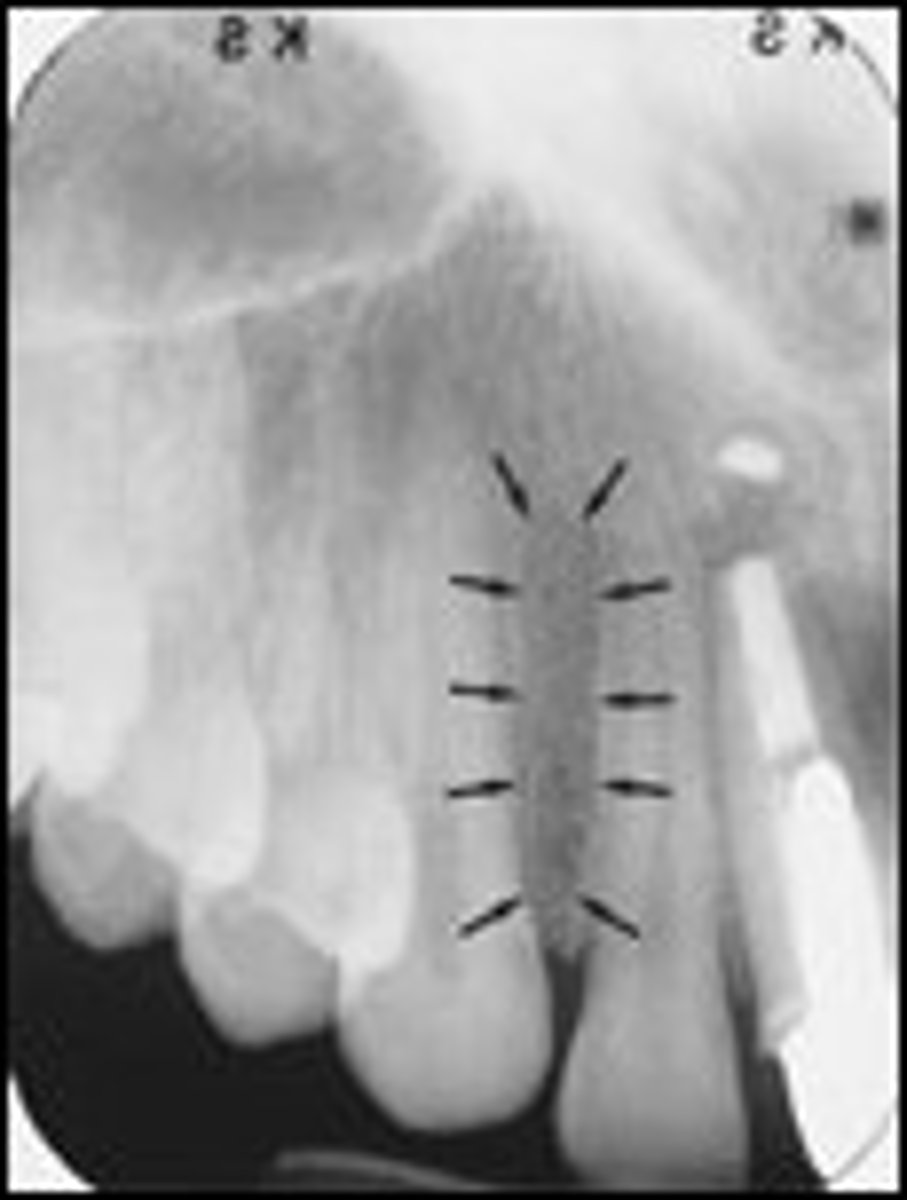

where can you see the genial tubercles in a radiograph

apices of 41/31

where can you see the lingual foramen in a radiograph

apcies of 41/31

does the genial tubercles appear radiopaque or radiolucent in a radiograph

radiopaque

does the lingual foramen appear radiopaque or radiolucent in a radiograph

radiolucent